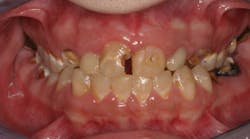

For example, one patient of a general dental practice had a caries-free history for 35 years. He ceased smoking traditional cigarettes and decided to vape as he thought this was a healthier alternative. Within a year, cervical enamel demineralization and interproximal lesions were present on the mandibular anterior sextant, consistent with the primary point of contact of the e-liquid aerosol (figure 2).

Figure 2: Effects of e-cigarette usage